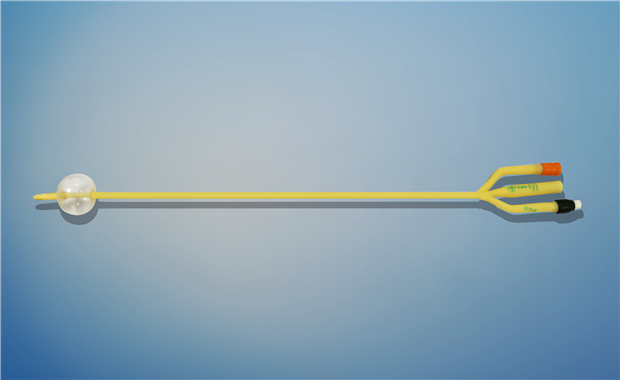

【產品名稱】一次性使用無菌導尿管(取樣型使用) 【型號】雙腔氣囊取樣型 【規格】:12FR-26FR 【主要結構、性能】由膠乳為主要原材料制成���,可配卡片����。

型號:雙腔氣囊標準型規格:雙腔氣囊標準型:12Fr(5-10mL)、12Fr(30mL)�、14Fr(5-10ml)、14Fr(30mL)���、16Fr(5-10mL)����、16Fr(30mL)、18Fr(5-15mL)�、18Fr(30mL)、20Fr(30mL)����、20Fr(50mL)���、22Fr(30mL)�、22Fr(50mL)...